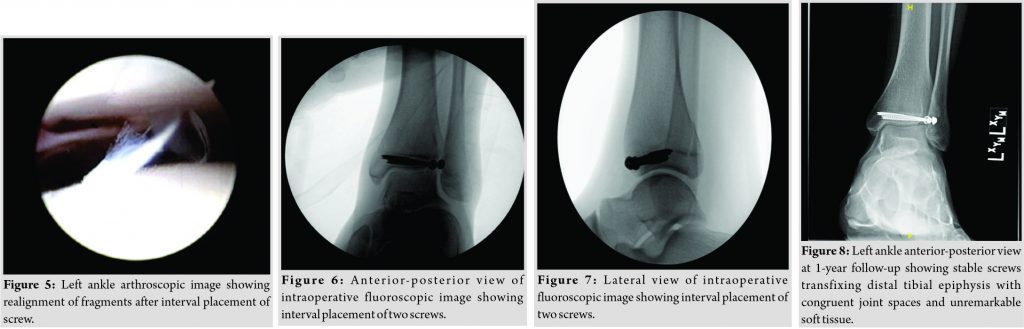

The decision was made to treat surgically based on the size of the articular step-off (2.5 mm) of the epiphyseal fragment. The tibialis anterior tendon and superficial peroneal tendons were marked out on the patient’s skin. An anteromedial portal for ankle arthroscopy was made and the scope was inserted. A diagnostic scope confirmed the presence of a Tillaux fracture over the anterolateral aspect of the left ankle. Soft tissue was present in the fracture site so an anterolateral portal just lateral to the superficial peroneal nerve was made and a chondrotome was inserted to debride the soft tissues. A dental pick was used to hold the fracture and reduce it under direct arthroscopic visualization. K-wires held the reduction in place while radiographs were obtained to confirm the reduction radiographically. An additional K-wire was placed to be more parallel with the joint, after which the non-parallel K-wire was removed. The K-wires were removed and measured and two 4 mm cannulated screws were then inserted into the distal tibia and visualized arthroscopically and radiographically (Fig. 4, 5, 6 and 7). Final radiographs were taken and the procedure was deemed successful. The posterior malleolus fracture was also visualized on these radiographs, which was confirmed to be non-displaced. Thus, the decision was made to not use any hardware for fixation and to treat this fracture closed without fixation. The patient’s left ankle was then placed in a shortleg plaster splint with instructions to remain non-weight-bearing and return to clinic in 2 weeks.

At 2 weeks postoperatively, the patient was not having any significant pain and could freely move his toes in the splint. The splint was removed and replaced with another shortleg plaster splint with continued non-weight-bearing status. Ankle strengthening and range of motion exercises were allowed to take place starting at 4 weeks postoperatively, with the patient transitioned to a controlled ankle movement (CAM) walking boot and continued non-weight-bearing status. At 8 weeks postoperatively, the patient was allowed to start balancing on his left ankle for activities of daily living and weight-shifting only, with non-weight-bearing status while walking. By 12 weeks postoperatively, the patient had weaned himself out of his CAM boot and into an aircast splint though he remained non-weight-bearing. He was tolerating weight-shifting and balancing well. At this time, the decision was made to allow him to begin weight-bearing as tolerated. At 20 weeks postoperatively, he was tolerating weight-bearing while walking and had no complaints of pain. Normal strength of the ankle joint was noted with active range of motion of 30° of plantar flexion and 20° of dorsiflexion. At 1 year postoperatively, the patient had returned to participatein athletics without restrictions and reported no pain with activity. He has retained full strength of the ankle joint and had increased his range of motion to 45° of plantar flexion and 30° of dorsiflexion. Final radiographs (Fig. 8) of the ankle show the fracture healing with no loosening of hardware.